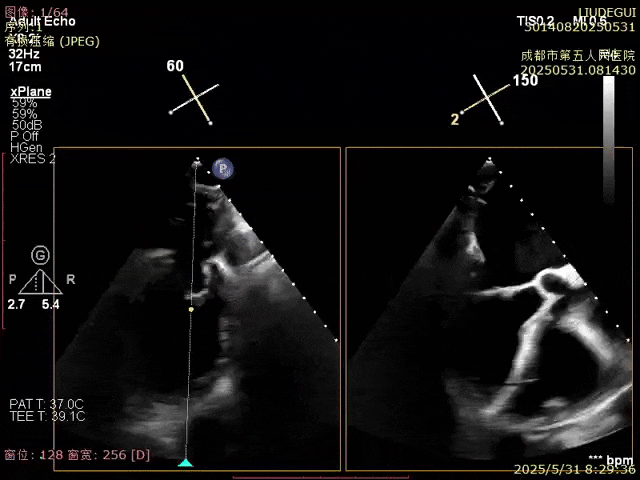

使用二尖瓣夾進行瓣葉捕獲,并進行夾合

確認夾合位置及效果